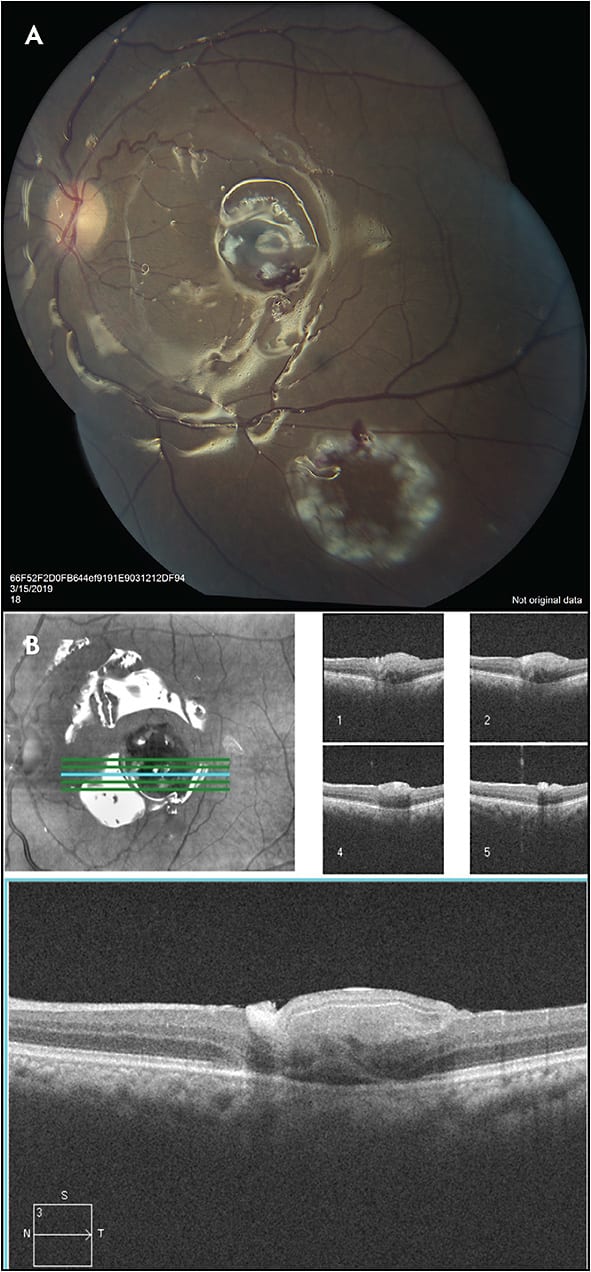

A 64-year-old male presented complaining of blurry vision in the left eye for 30 years, following left-sided head trauma (Figure 1). He was diagnosed with a very large macular hole and was told by multiple providers that there was nothing that could be done for his vision. He described a very bothersome “swirl” in his central vision and expressed an interest in doing anything possible in order to improve his symptoms. The smallest diameter of the hole was 1,160 microns and the largest diameter at the base of the hole was 1,786 microns. After a discussion of various surgical options and likely success rates, the patient decided to proceed with an autologous retinal patch graft surgery.

The patient was managed with a 23-gauge PPV, membrane peeling, autologous free retinal patch graft, endolaser, and perfluorocarbon injection, and then 1 week later, he underwent perfluorocarbon removal (Figure 2). Visual acuity improved from 20/200 at baseline to 20/150 at postoperative month 2 (Figure 3), and finally to 20/80 after cataract was removed 5 months later. OCTs continues to show that the macular hole has closed (Figures 4 and 5), with the most recent follow-up at 11 months after the surgery. OCT angiography shows no graft revascularization, which preserves the foveal avascular zone. The patient continues to enjoy disappearance of the swirl and dense blind spot in his vision, and reports improved binocular vision.